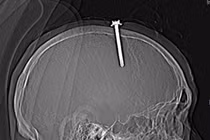

Dị vật xuyên màng não là cấp cứu ngoại khoa nghiêm trọng, tùy theo vị trí tổn thương của dị vật mà có thể dẫn đến các biến chứng nguy hiểm như: yếu liệt chi, rối loạn chức năng sống, áp xe não, thậm chí tử vong.

Bé trai nhập viện trong tình trạng đa chấn thương, xương sọ bị vỡ lún có tràn khí và chảy máu dưới màng cứng... Thực tế có rất nhiều trẻ bị chó cắn do sự bất cẩn của người lớn nên cần chú ý.